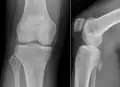

- Röntgenbilder

-

Kartilaginäre Exostose an einem Oberschenkelknochen -

Kartilaginäre Exostose mit breiter Basis an einem Oberarmknochen -